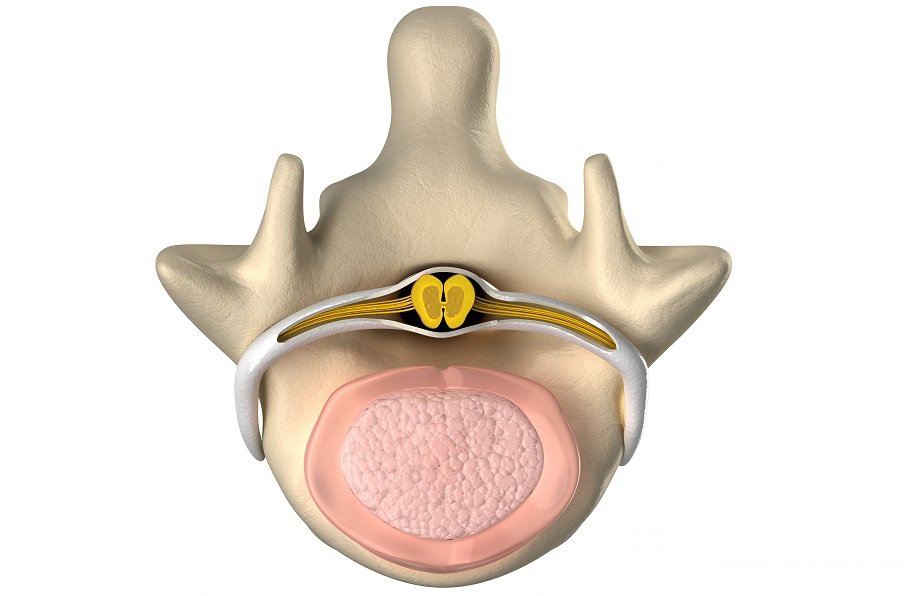

Расположен спинной мозг в позвоночном канале. Сзади и спереди находятся две борозды, благодаря которым мозг делится на правую и левую половину. Он покрыт тремя оболочками: сосудистой, паутинной и твердой. Пространство между сосудистой и паутинной оболочками заполнено спинномозговой жидкостью.

В центре спинного мозга можно увидеть серое вещество, на срезе по форме напоминающее бабочку. Состоит серое вещество из двигательных и вставочных нейронов. Наружный слой мозга представляет собой белое вещество аксонов, собранных в нисходящие и восходящие проводящие пути.

В сером веществе различают два типа рогов: передние, в которых находятся двигательные нейроны, и задние, место расположения вставочных нейронов.